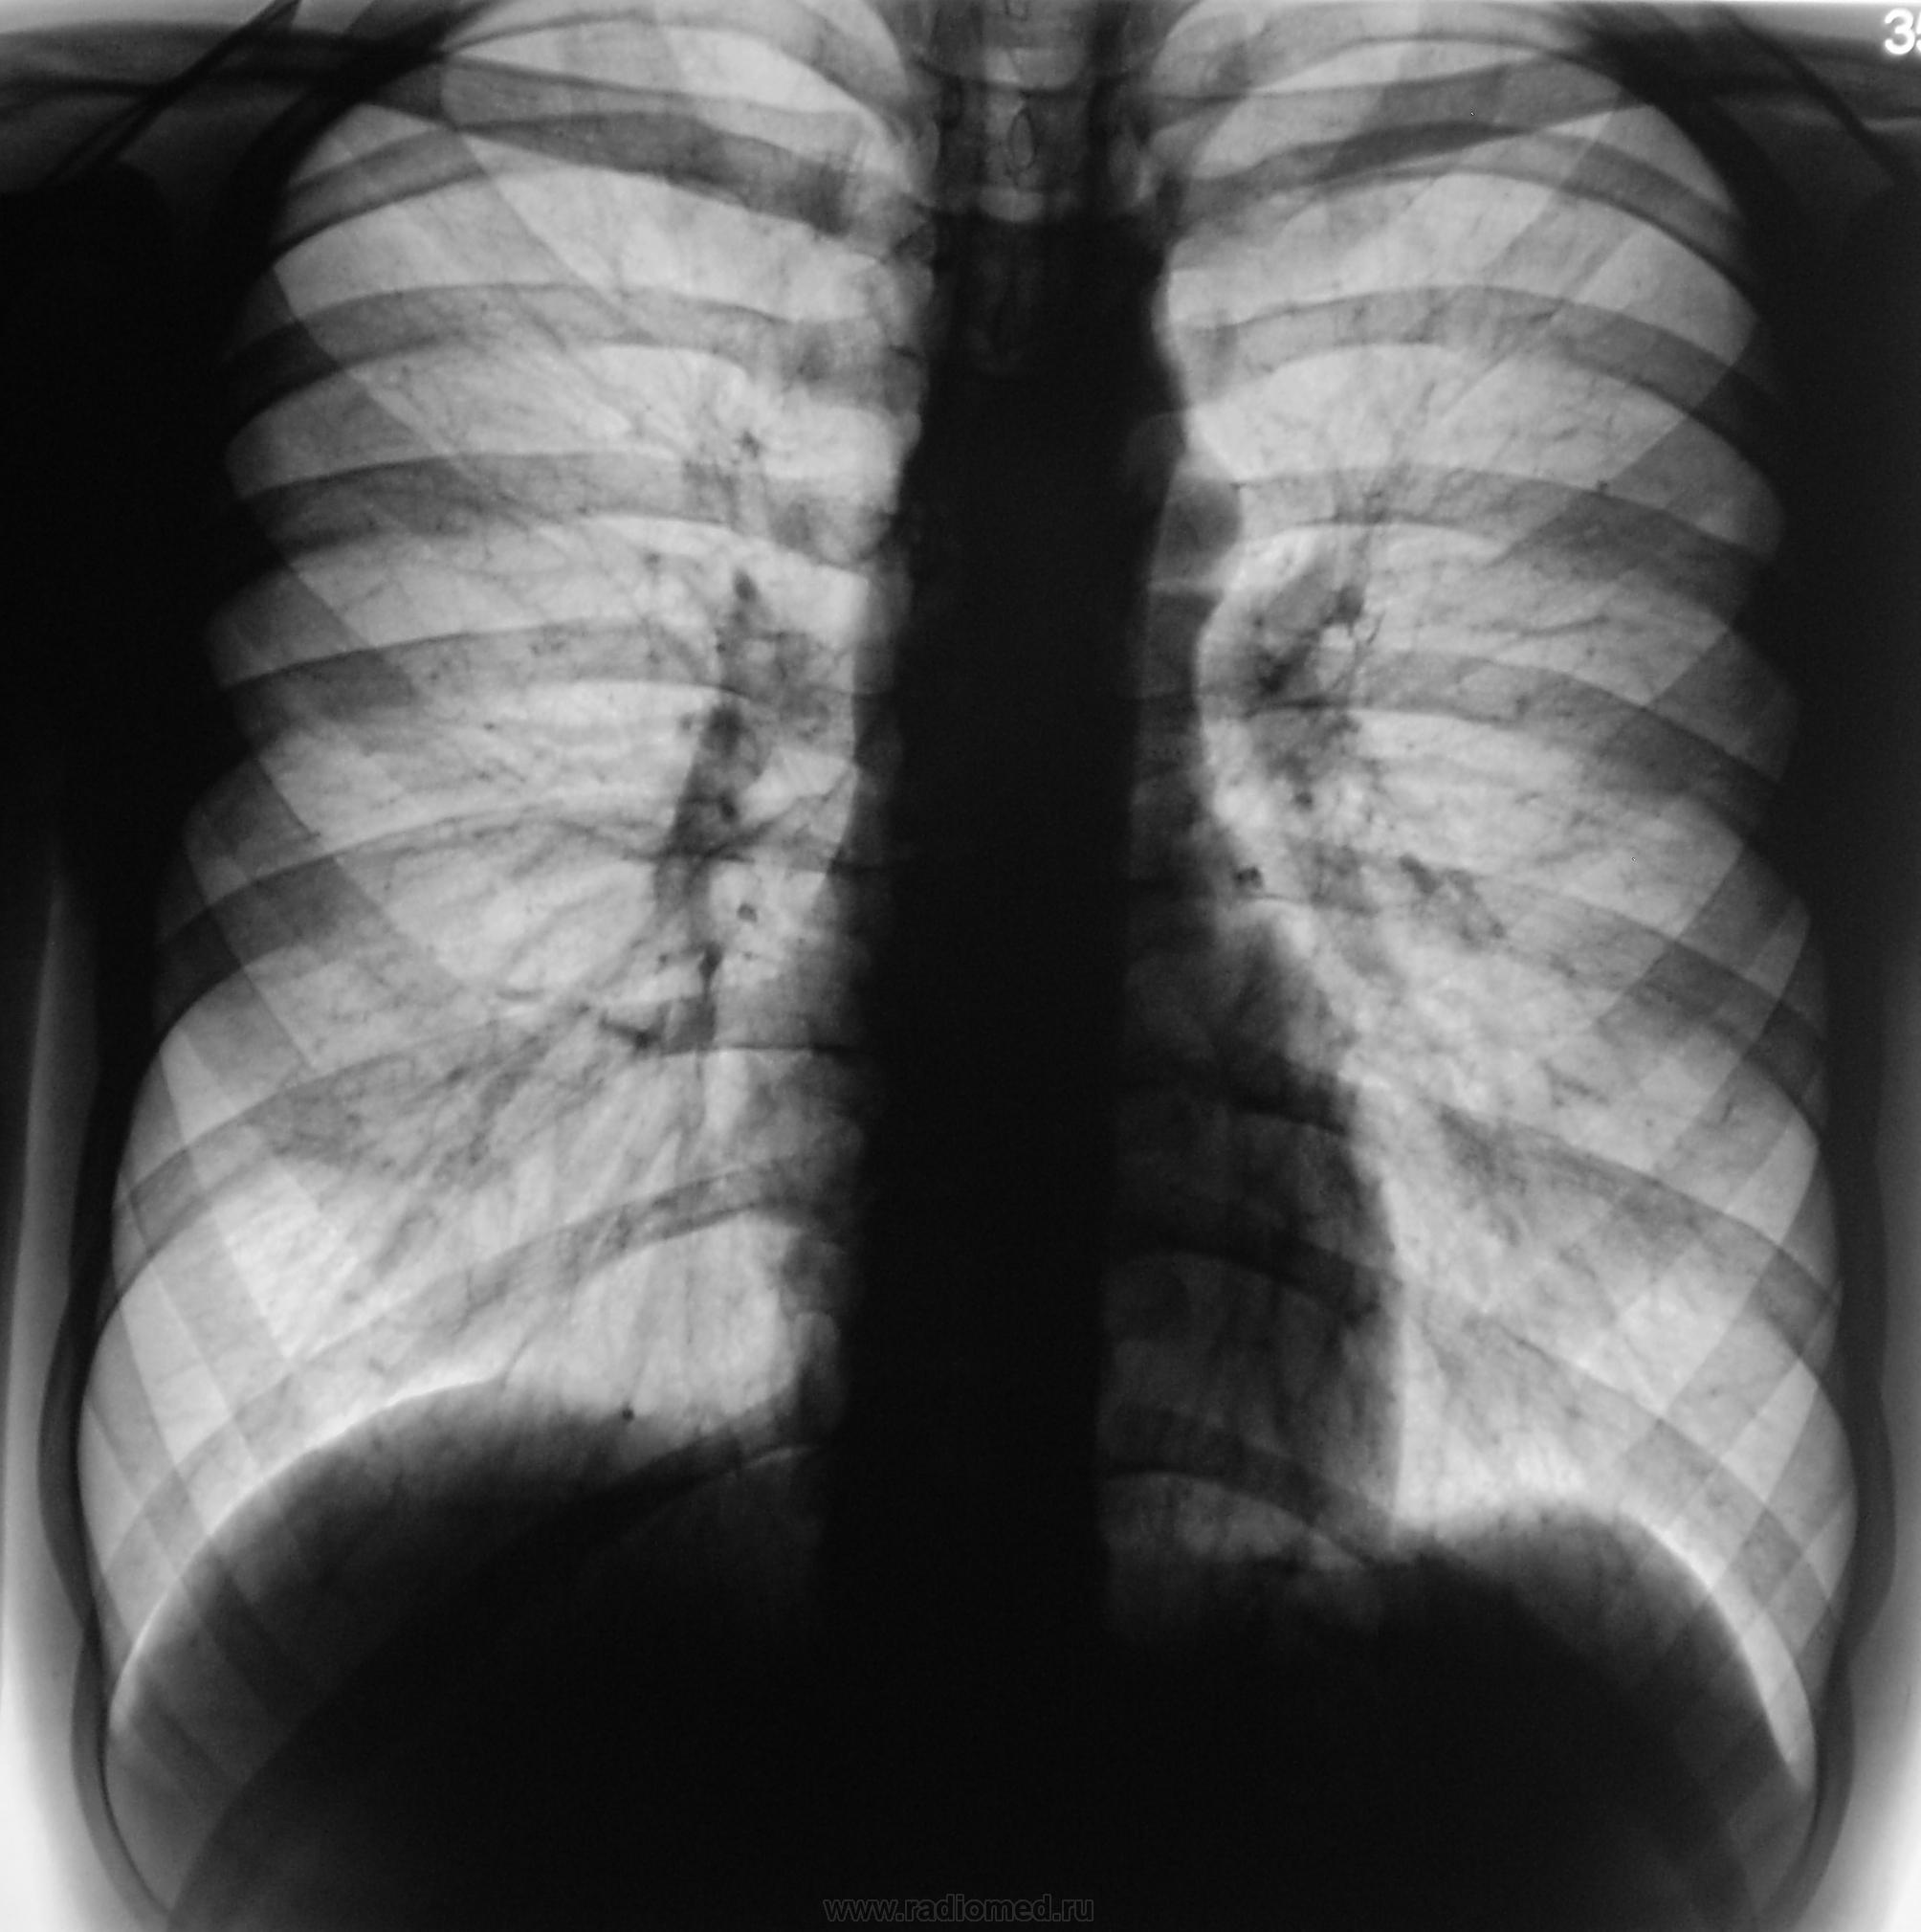

Произведена рентгенограмма в прямой проекции.

Смотрите рисунок.  Заключение написано на снимке. Кроме очагов в легких, имеется увеличение паратрахеального лимфатического узла. В ПТД на лечение.  Nikolas

Заключение написано на снимке. Кроме очагов в легких, имеется увеличение паратрахеального лимфатического узла. В ПТД на лечение.  Nikolas

Дело в том, что этого пациента я зацепил еще год тому назад.

Снимки ниже.